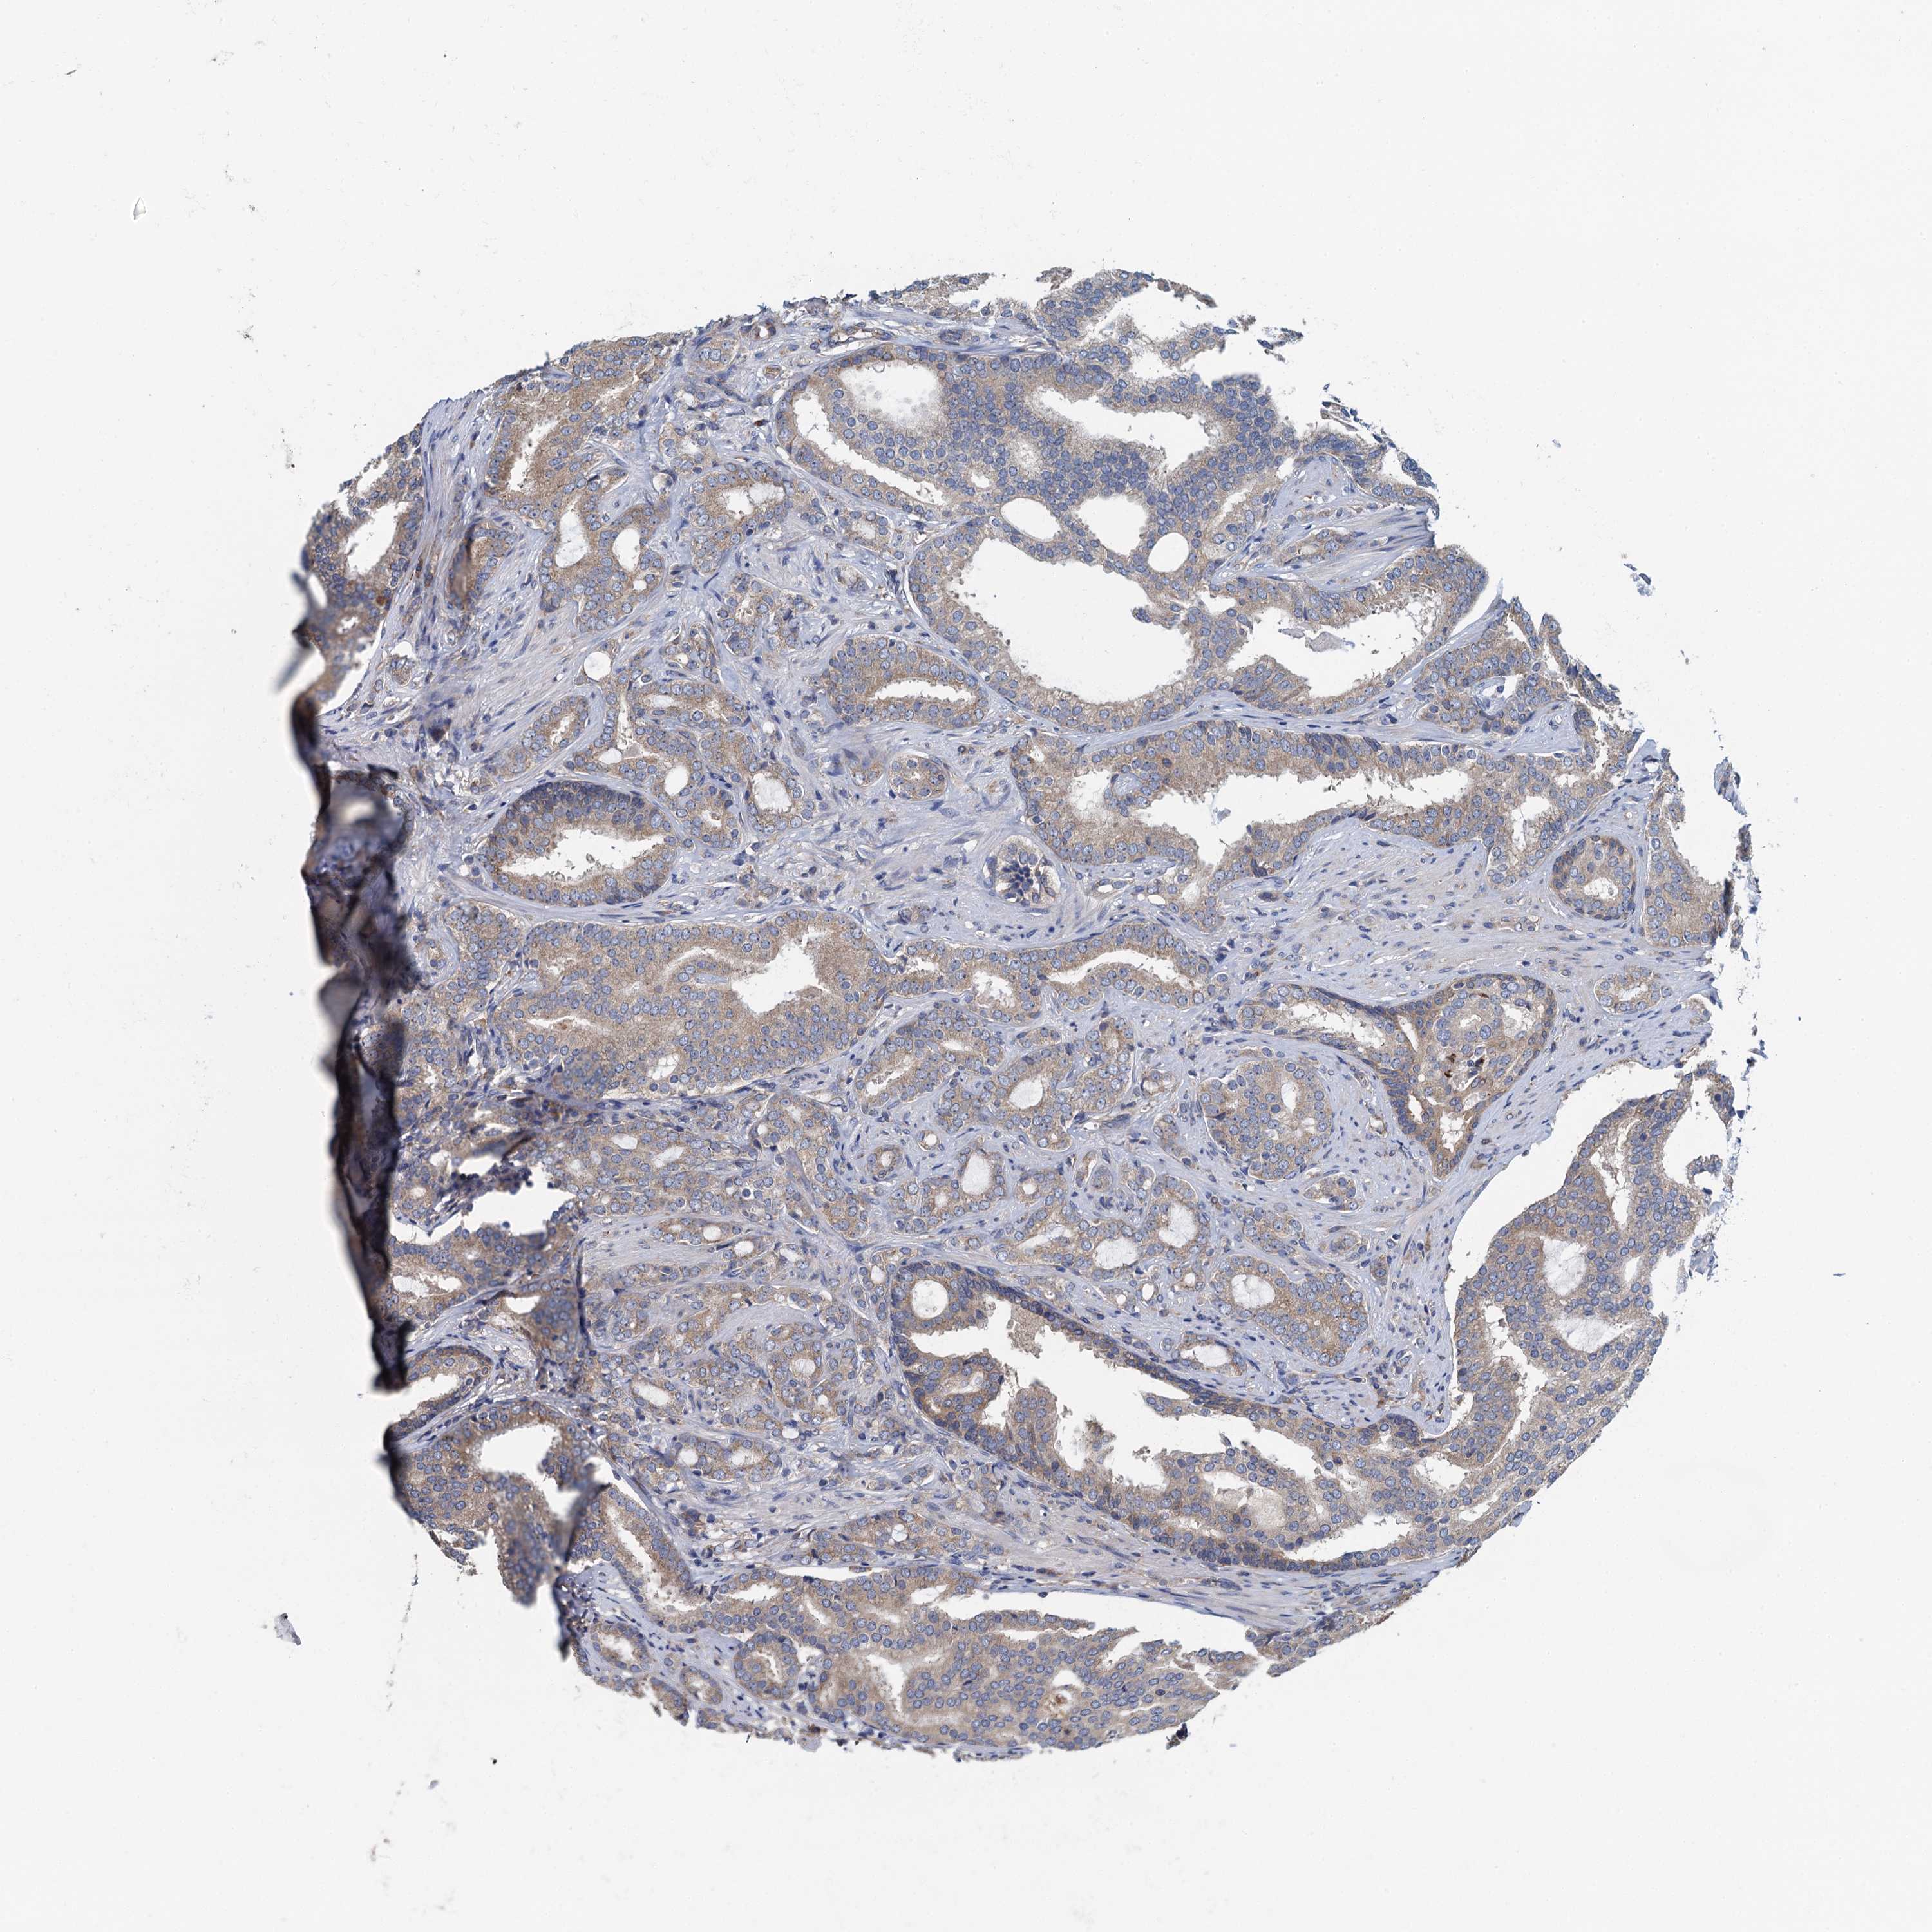

PROSTATE CANCER - Protein expressioni

A mouse-over function shows sample information and annotation data. Click on an image to view it in a full screen mode. Samples can be filtered based on level of antibody staining by selecting one or several of the following categories: high, medium, low and not detected. The assay and annotation is described here.

Note that samples used for immunohistochemistry by the Human Protein Atlas do not correspond to samples in the TCGA dataset.

Antibody stainingi

Antibody staining in the annotated cell types in the current human tissue is reported as not detected, low, medium, or high, based on conventional immunohistochemistry profiling in selected tissues. This score is based on the combination of the staining intensity and fraction of stained cells.

Each image is clickable and will lead to virtual microscopy that enables deeper exploration of all samples and also displays staining intensity scores, fraction scores and subcellular localization as well as patient and tissue information for each sample.

Antibody HPA041328

Antibody HPA044225

Staining

High

Medium

Low

Not detected

Intensity

Strong

Moderate

Weak

Negative

Quantity

>75%

75%-25%

<25%

None

Location

Nuclear

Cytoplasmic/membranous

Cytoplasmic/membranous,nuclear

Adenocarcinoma, NOS

Adenocarcinoma, High grade

Adenocarcinoma, Low grade